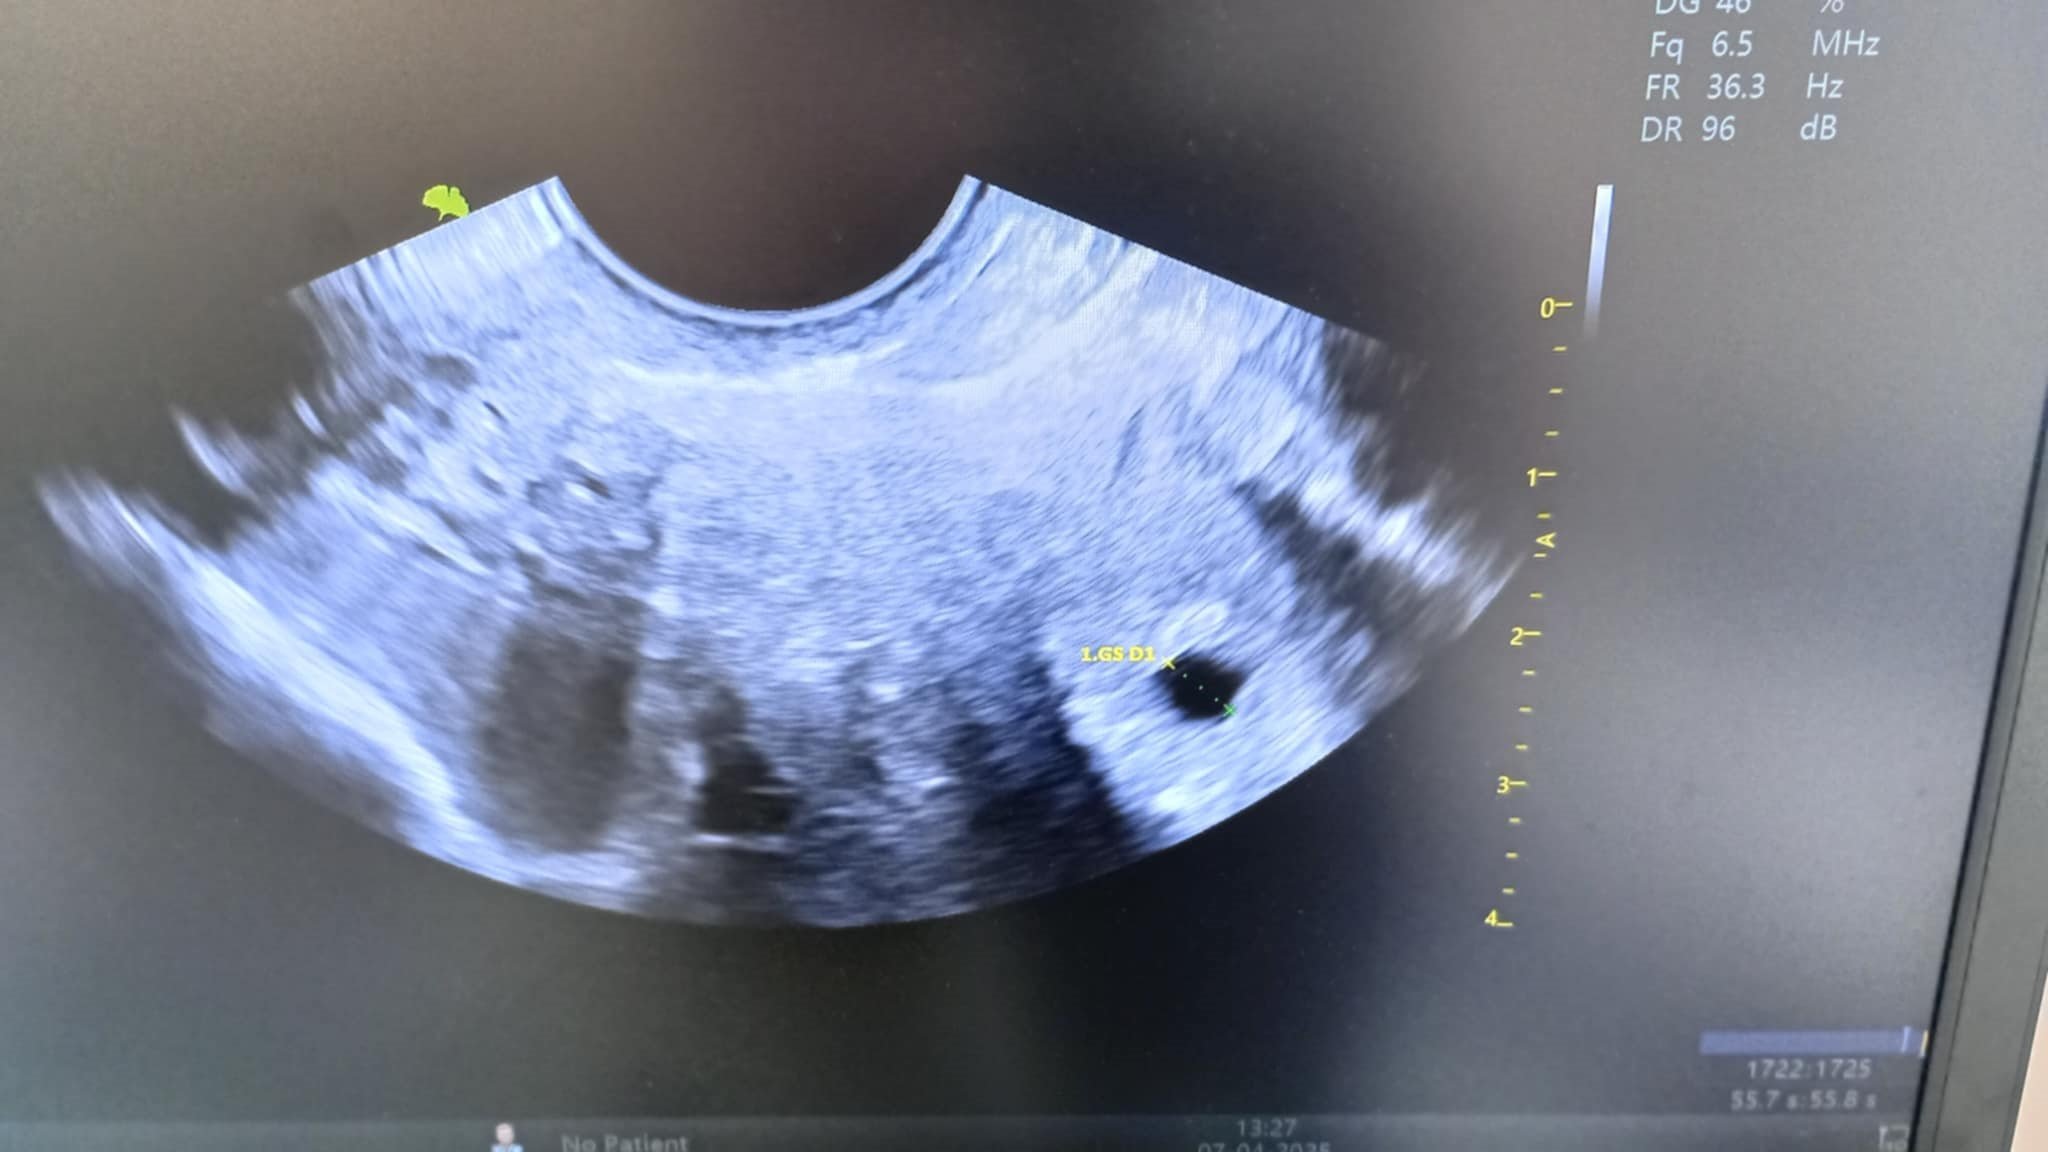

Какво представляват черните точки в матката на ехографската снимка?

Кога обикновено може да се види ембрионът на ултразвукова снимка?